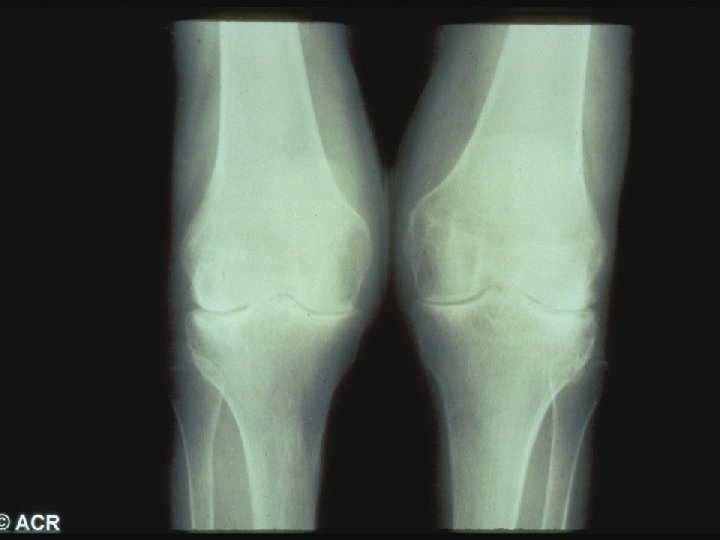

Site of Onset Joint Involvement Mean % of Patients MCP, PIP 91 Wrist 78 Knees 64 Shoulders 65 Ankles 50 Feet 43 Elbows 38 Hips 17

Baseline Evaluation of Patients · Physical Examination - Documentation of actively inflamed joints - Documentation of mechanical joint problems: loss of motion, crepitus, instability, deformity - Documentation of extra-articular manifestations - Optho, cardiac, pulmonary, rash, LAD

Baseline Evaluation of Patients · Radiography - Wrist and hands - Feet - Other symptomatic joints

Sharp Scores of Radiographic Progression Erosion scores · 17 joints of each hand/wrist · 6 joints of each forefoot · Scale: 0– 5; Total score: 0– 230 Joint space narrowing (JSN) scores · 16 joints of each hand/wrist · 5 joints of each forefoot · Scale: 0– 4; Total score: 0– 168 Total Sharp score · Add erosion and JSN scores · Total score: 0– 398 Sharp JT, et al. Arthritis Rheum. 1985; 28: 1326– 1335 van der Heijde DM, et al. J Rheumatol. 1995; 22: 1792– 1796.

Joint Erosions Occur Early in RA Maximum % Joints Affected · Up to 93% of patients with <2 years of RA may have radiographic abnormalities · Erosions can be detected by MRI within 4 months of RA onset Hand MTP All · Rate of progression is significantly more rapid in the first year than in the second and third years Year Fuchs HA et al. J Rheumatol. 1989; 16: 585 -591. Mc. Queen FM et al. Ann Rheum Dis. 1998; 57: 350 -356. van der Heijde DM et al. J Rheumatol. 1995; 22: 1792 -1796.